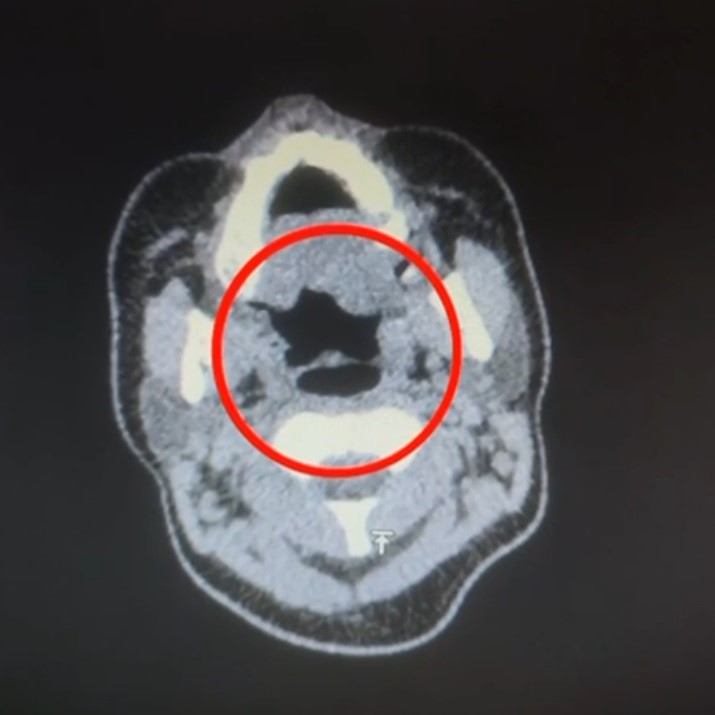

Uluslararası uyuşturucu madde ticareti yapan kuryenin midesinde 50 adet kapsül şeklinde 500 gram uyuşturucu madde ele geçirildi.

Kayseri İl Emniyet Müdürlüğü Narkotik Suçlarla Mücadele Şube Müdürlüğü ekipleri, uluslararası uyuşturucu madde ticareti yapan kurye şahıslara yönelik operasyon düzenledi. Operasyonda A.R.’yi (27) gözaltına alan ekipler, şahsı hastane muayenesine götürdü. Şüphelinin yapılan iç beden muayenesinde, mide kısmında bulunduğu tespit edilen 50 adet kapsül şeklinde toplam 500 gram uyuşturucu madde ele geçirildi. ‘Uyuşturucu madde ticareti yapmak’ suçundan gözaltına alınan şüpheli emniyete götürüldü. iha